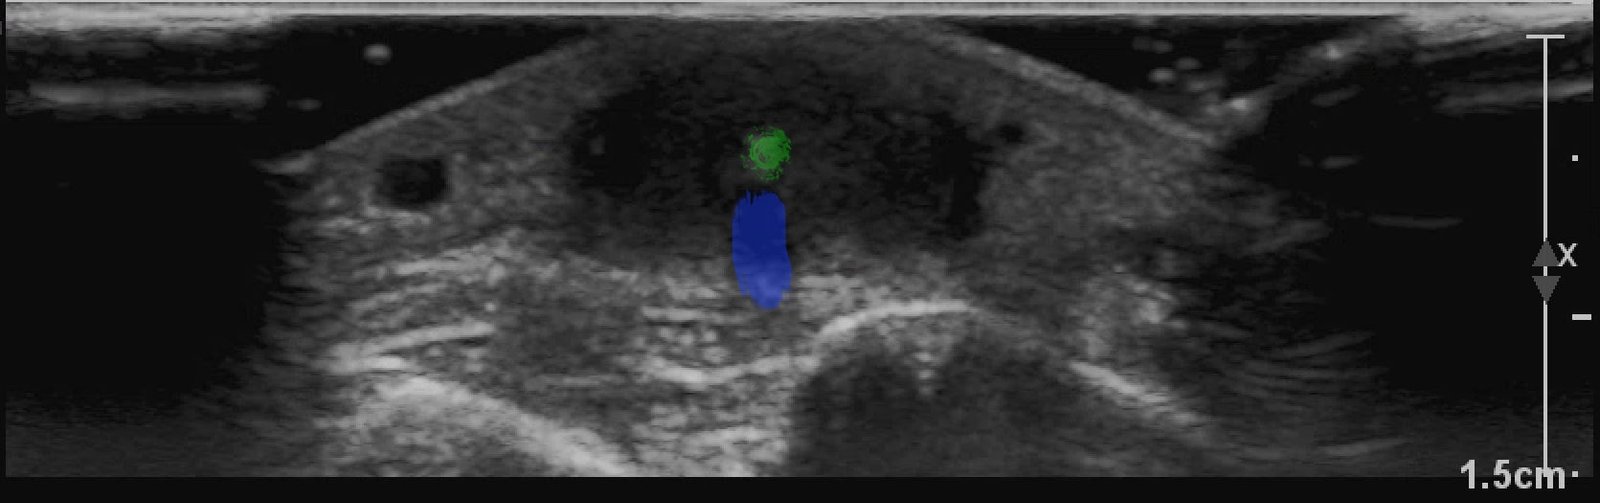

X-rays of the foot were obtained and no radiopaque foreign body was visualized. Due to high clinical suspicion for retained foreign body, a point-of-care ultrasound was performed by applying a high-frequency linear probe at the area of discomfort. In the long axis an ovoid focus of hypoechogenicity (orange outline) is visualized. Within this finding there is a linear focus (yellow line) of increased echogenicity measuring 1 mm in diameter and 1 cm in length. On short axis view, a rectangle focus (green dot) demonstrating shadowing (blue highlight) is seen.

Given the evidence of foreign body on ultrasound, incision and drainage was performed. It resulted in the removal of a 1 cm splinter along with small amount of purulent and serous fluid.